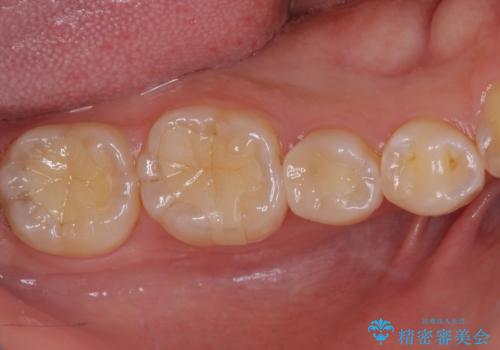

ディープバイトが改善されたことで、顎への負担が軽減され、更には上顎前歯の突出感も改善することができました。

矯正治療後には欠けてしまった修復物をセラミックインレーにて修復治療しました。